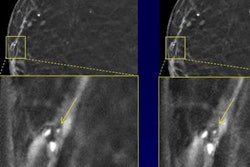

The potential for AI to enable significant reductions in radiation dose is one of the technology's most promising applications in medical imaging. At the recent SPIE Medical Imaging 2018 conference in Houston, a multi-institutional team found that a deep learning-based image processing technique may be able to sharply lower radiation dose from digital breast tomosynthesis exams -- perhaps by as much as 80%. How did the researchers do it? Click here for our coverage.